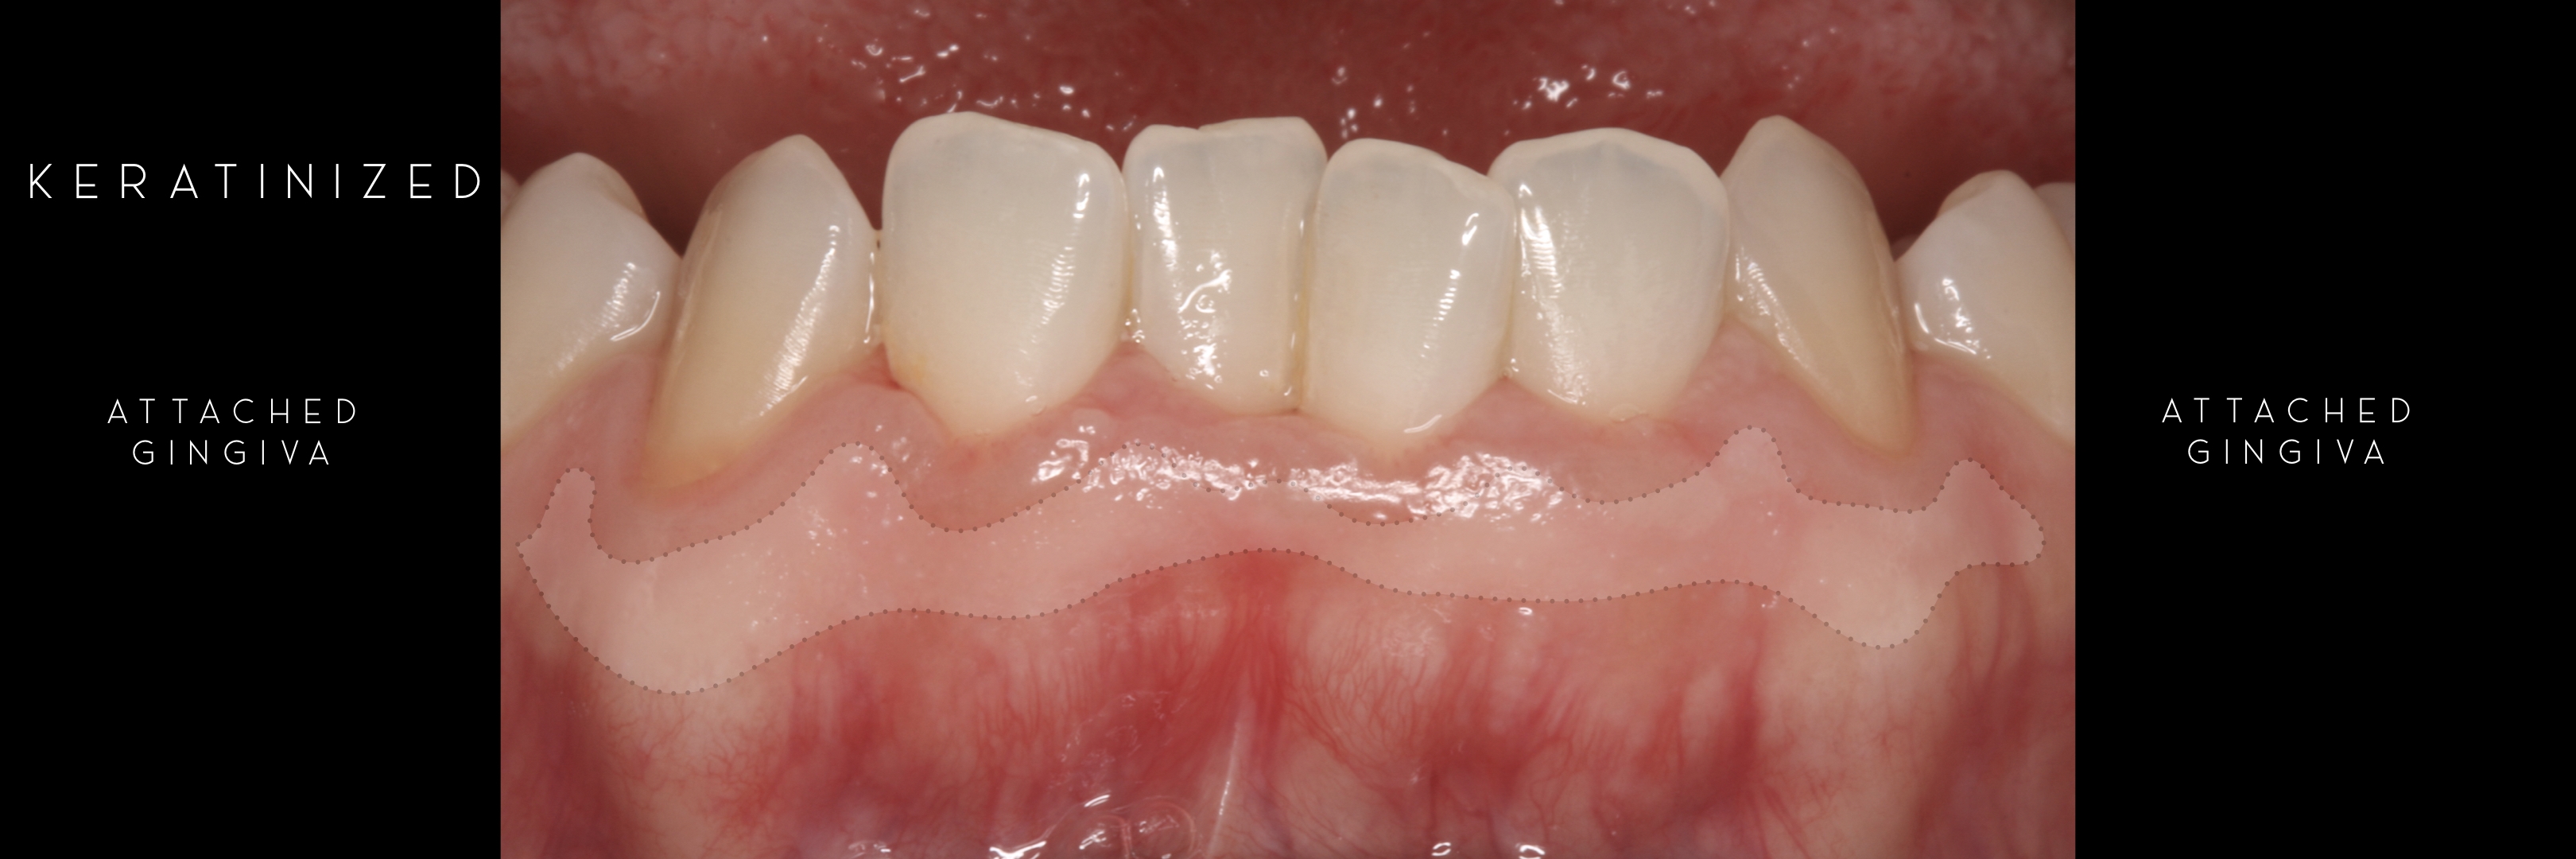

KERATINIZED gingiva includes

the free gingiva

(marginal gingiva & papillae)

and the attached gingiva extending from the gingival mar­gin to the mucogingival junction.

Also keratinized is the hard palate mucosa.

Generally we tend to forget about these 2 parameters, free and the attached gingiva are both essential parts of the keratinized gingiva.

This meaning that keratinized (load bearing capacity) is a mechanical characteristic that makes up for attached gingiva, providing it's immobility,  but also is of such importance as the thickness it provides around whatever perforates the epithelium, be it implants or teeth, being also keratinized (having load bearing capacity) at this location.

The width of the keratinized gingiva may vary between 1 and 9mm.